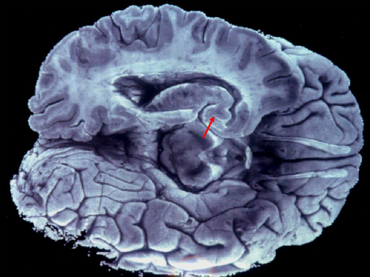

CIUDAD DE MÉXICO (17/MAR/2016).- Las alucinaciones auditivas y visuales son más frecuentes de lo que pudiera pensarse, y para que ocurran no se necesita algún tipo de sustancia, sino una falla entre el lóbulo frontal y la corteza cerebral.

John McGrath, especialista del Queensland Brain Institute, señaló que en ocasiones algo va mal en la relación lóbulo frontal-corteza cerebral, y se genera la falla de percepción o alucinación, publicó la Australian Broadcasting Corporation (ABC).

Puntualizó que cuando todo va bien, el lóbulo frontal está al mando y controla al conjunto del cerebro, pero situaciones como las señaladas, reducen su eficiencia y es cuando se puede crear la alucinación